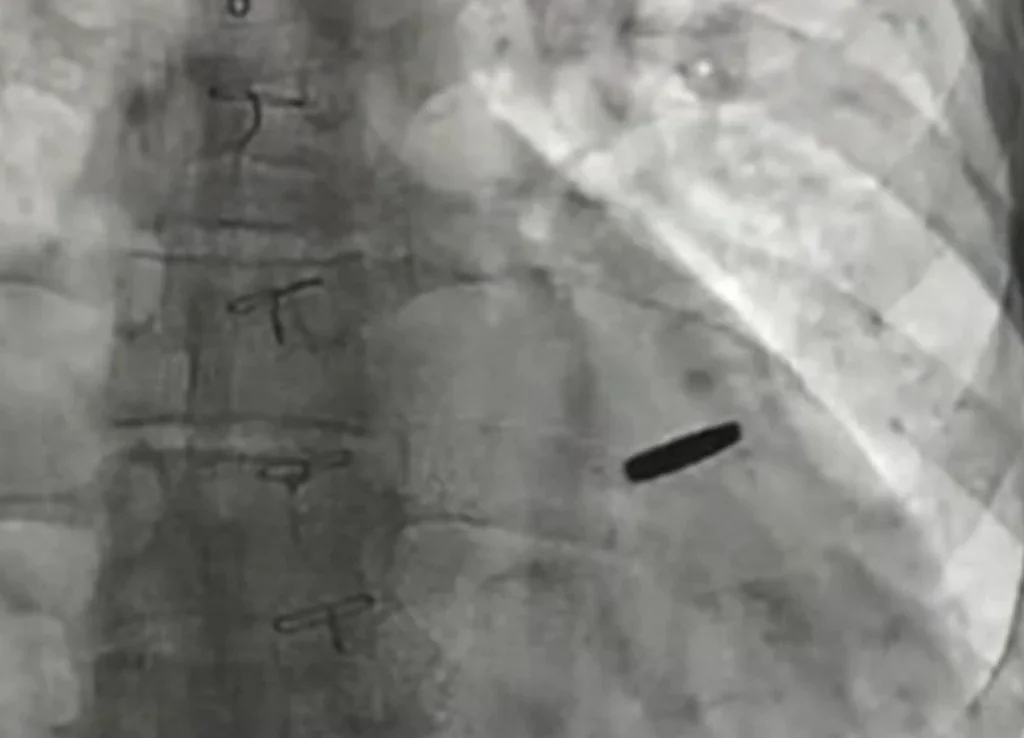

З серця звільненого з російського полону українського військового дістали кулю, з якою він прожив три роки.   Про це повідомив директор Інституту серця МОЗ України Борис Тодуров.  Поранений військовий захищав «Азовсталь» і потрапив до полону під час атаки на Маріуполь. Три роки він був у неволі, а два ...